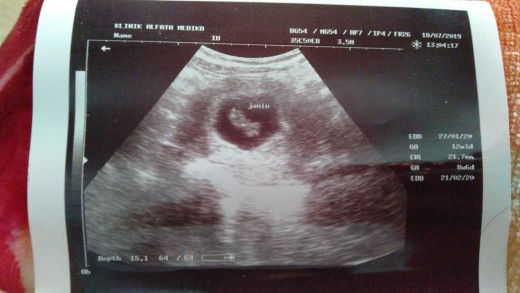

hasil usg

assalamu'alaikum bunda..sudah 2 hari ini saya buka aplikasi ini karna saya sedih kalo lihat usia kandungan saya..3 hari yg lalu saya pernah bertanya tentang bercak/plek,tadinya saya pikir cuma plek biasa,besoknya saya periksa kepuskesmas sekalian mau USG,kata bidannya usgnya lagi gk ada dokternya & harus kerumah sakit saja besok pagi karena saya datang kepuskesmas jam 11 siang,jadi kalo langsung ke RS juga pasti dh tutup no antriannya karena jarak puskesmas & RS juga jauh..akhirnya karena tanggung saya sudah jalan sudah jauh dari rumah karena saya mikir jalannya juga rusak,mending sekalian USG walaupun bukan dirumah sakit. Akhirnya saya nanya2 tempat USG yg siang bisa USG,dan dikasih tau temanlah ada salah satu klinik,akhirnya saya usg,& kata dokter gk kenapa2 cuma butuh bedtres yg cukup jaga pola makan buah & sayur yg cukup,enak banget penjelasan dokternya.. Setelah itu saya pulang & istirahat tapi setiap saya cek masih tetap pendarahan bahkan lebih banyak dari biasanya,saya pikir cuma pendarahan biasa saja karena saya pernah ketemu orang yg selama hamil pendarahan terus bahkan darahnya lebih banyak,& gk ada rasa sakit sekalipun & besok malamnya mulai terasa sakit tapi gk saya anggap karena cuma cenat cenut aja dikira saya bawaan bayi,setelah jam 10 sampai jam 12 makin mulesnya makin sering makin sakit akhirnya setengah 1 kaluar darah banyak & akhirnya keluarlah calon baby-nya (keguguran)...ya Allah Bun sedih ya rasanya kehilangan semoga bunda2 disini kandungannya selalu sehat ya sampe persalinan nanti.

usg

Hai bunda-bunda saya ingin USG usia kehamilan 11 week kira2 sudah kelihatan belum ya?? & Biaya usg biasanya berapa?? Soalnya takut biayanya kurang